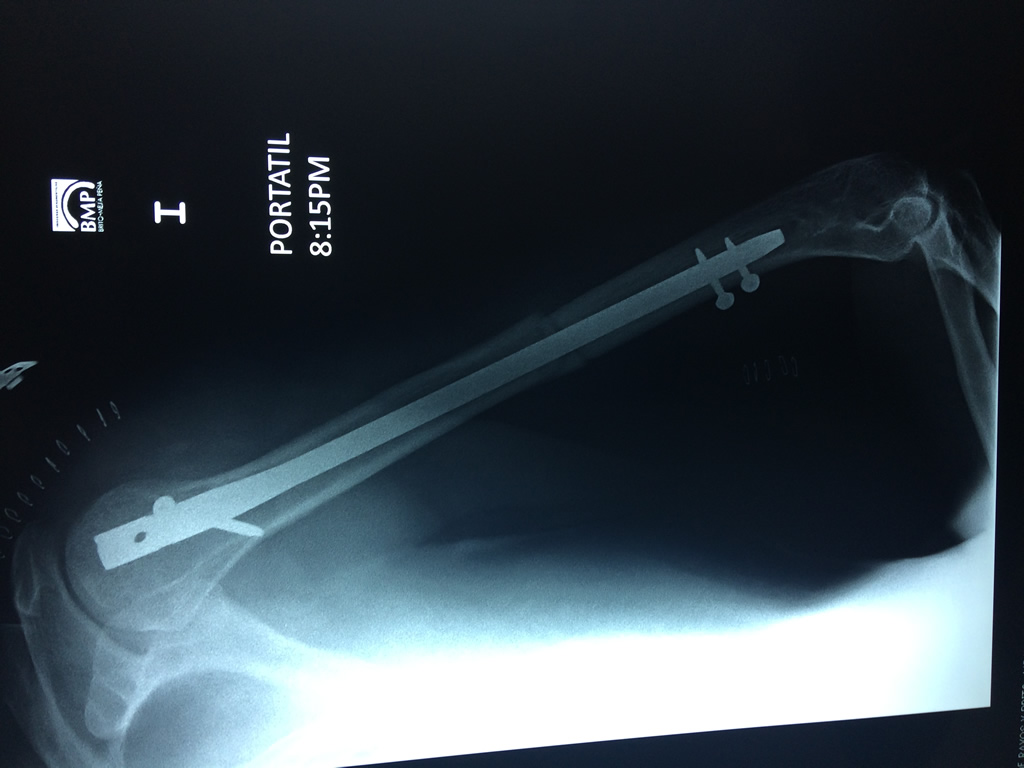

Cirugías de Cadera

El Húmero (en latín, humerus) es el hueso más largo de las extremidades superiores en el ser humano. Forma parte del esqueleto apendicular superior y está ubicado en la región del brazo. ... El extremo proximal del húmero tiene la cabeza, cuellos quirúrgico y anatómico y tubérculos mayor y menor.